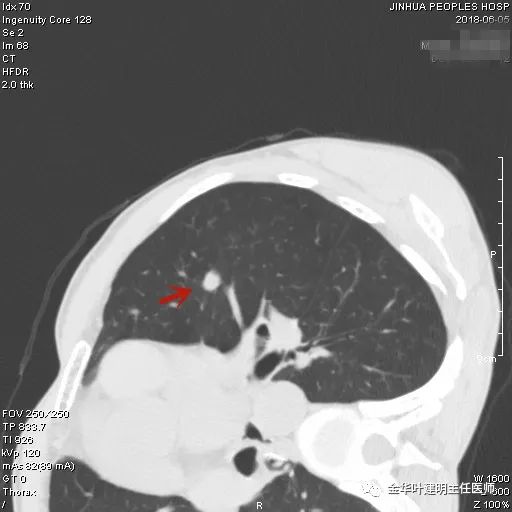

上图示浸润性腺癌典型表现。实性结节,有细毛刺征,有血管进入病灶,部分地方有浅分叶。